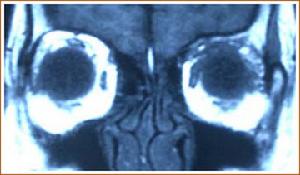

眼眶非霍奇金惡性淋巴腫瘤的分類雖然複雜臨床表現卻較為一致且多見於淚腺區,這是因正常淚腺內有淋巴組織存在的緣故一側或兩側眼瞼腫脹下垂,捫及無痛性硬性腫物眼球突出並向一側移位,球結膜水腫。因病變浸潤性增生,波及視神經和眼外肌,視力減退經常發生,眼球運動受限,甚者眼球固定結膜下侵犯可透過結膜看到粉色魚肉樣腫物惡性程度較高的腫瘤發展較快,眼瞼浸潤變硬遮住眼球,與眶內腫物連為一體。腫瘤發生的年齡和臨床表現與淋巴浸潤炎性假瘤頗為相似尤其是需要與淚腺炎型假瘤進行鑑別診斷眶內惡性淋巴瘤有時伴有其他部位淋巴結腫大需全身詳細檢查。

根據病史及臨床表現,並結合影像學檢查,診斷並不難最後確診還要靠活體組織檢查

鑑別診斷: 主要是和淚腺上皮性腫瘤鑑別後者為多回聲或中高反射。但和淚腺炎性假瘤區別困難必要時活檢證實診斷。最易和其混淆的是淋巴細胞性炎性假瘤,兩者在臨床和影像上均類似僅淋巴瘤年齡偏大最後鑑別需要病理證實。